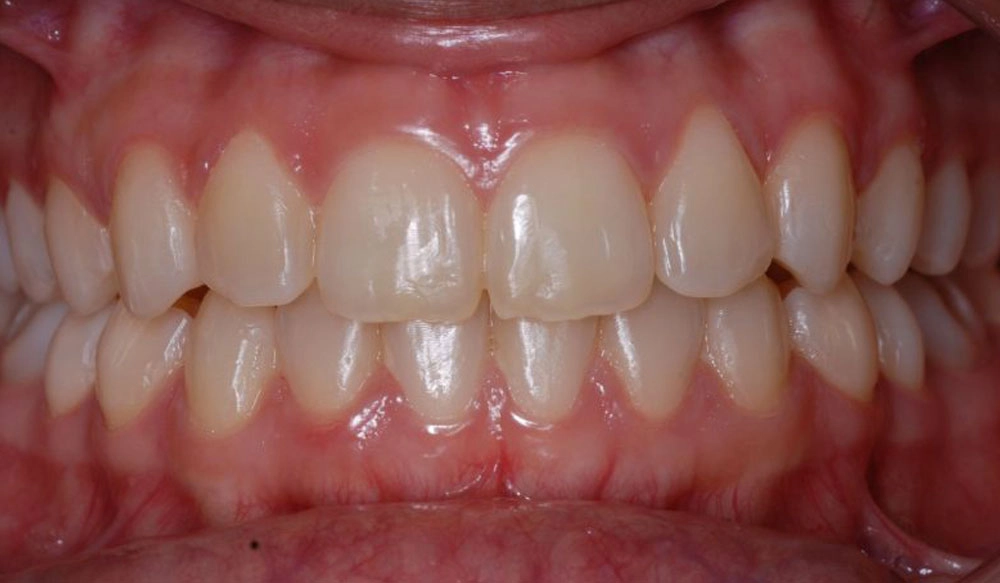

Class II

Class II — or "overbite" — is the condition in which the mesiobuccal cusp of the upper first molar is positioned mesially to the mesiobuccal groove of the lower first molar instead of both being aligned, affecting the occlusal relationship between both dental arches.

Patient Information:

Age: 24

Gender: Female

Invisalign Treatment Option: Invisalign Comprehensive

Total Treatment Time:

21 Months